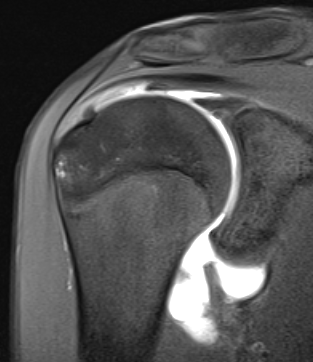

MRI

Normal humeral insertion of IGHL on left, HAGL with discontinuity of J sign on right